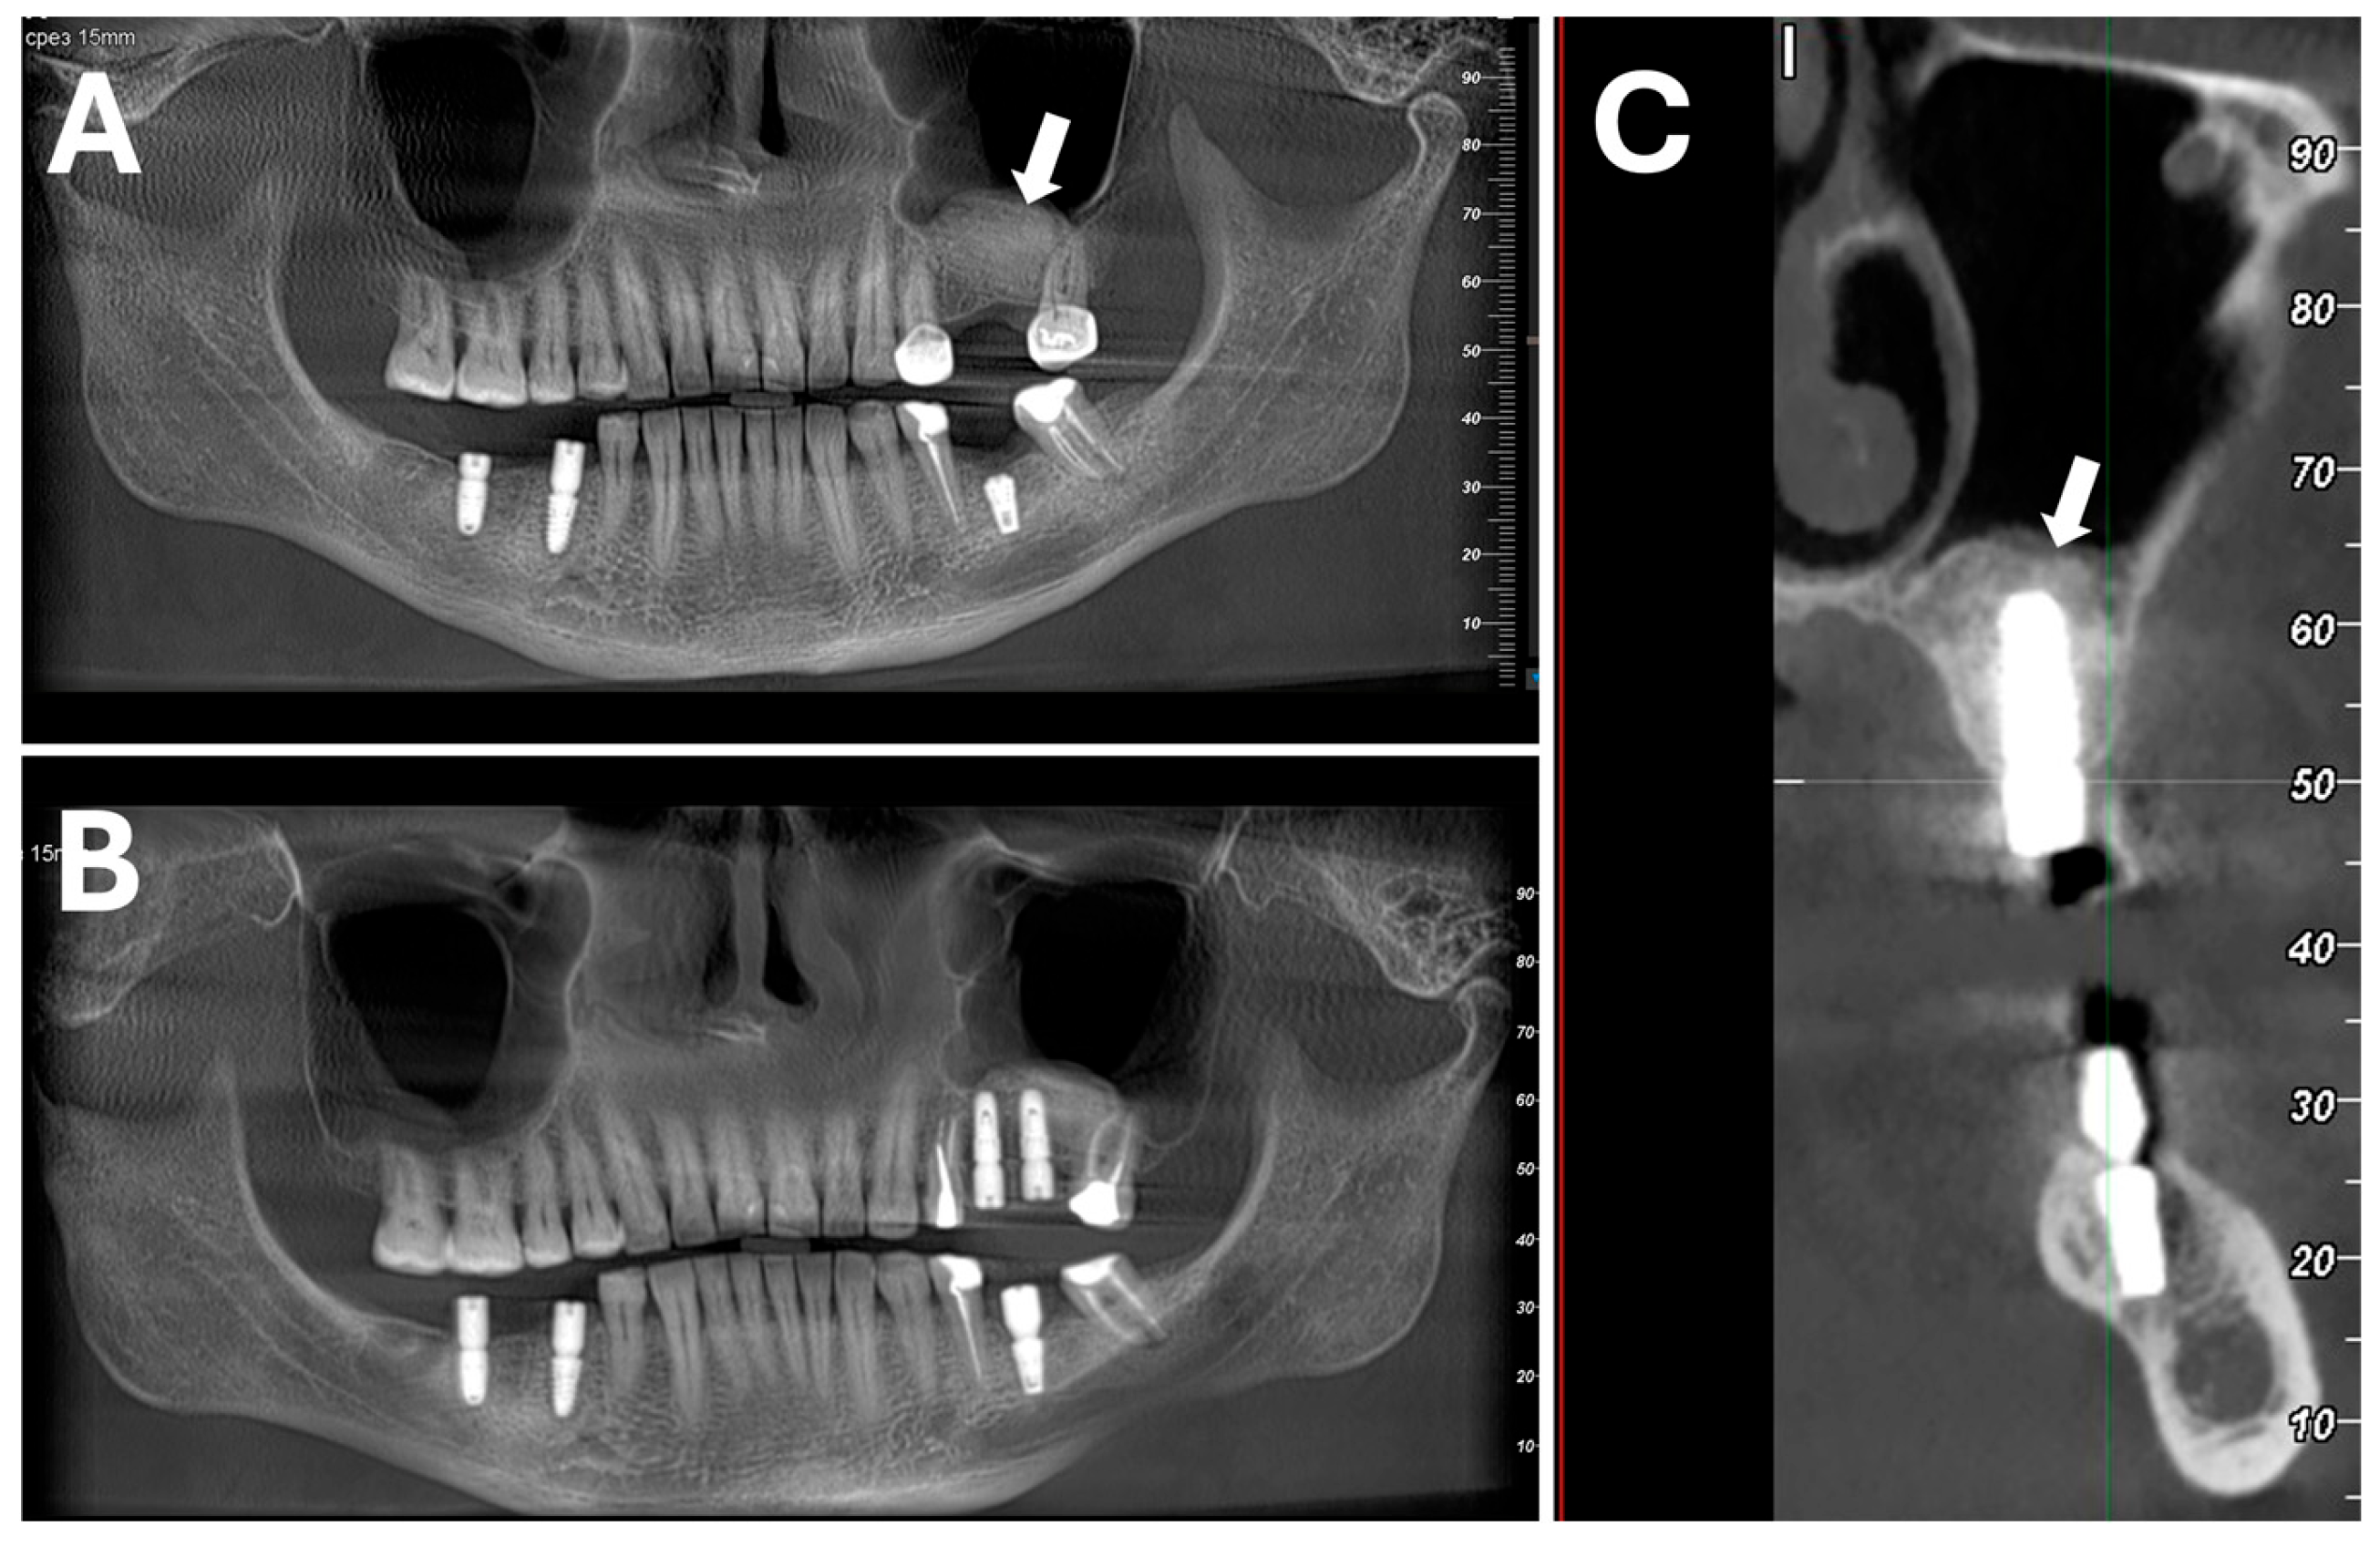

Host bone regeneration and tolerability were superior to both deproteinated xenograft and sham controls in a canine mandibular two-wall defect model examined at 4, 12, and 24 weeks after grafting. At 24 weeks, there was greater persistence of graft material in the deproteinized xenograft bone material group than in the porcine dentin group, demonstrating that the dentin graft is more rapidly resorbed than the well-established xenograft material commonly used in dental clinical practice. Tolerability and initial inflammatory reaction were similar to the control deproteinized material.

In a clinically relevant porcine extraction socket and sub-periosteum pouch model, there was excellent defect repair already at 2.5 months after grafting. Grafted areas were solid, dense, and stable, and X-rays showed homogenous radio-opacity. Histology showed new bone growth in close apposition to the grafted particles.

A well-designed, randomized, parallel-group, semi-double-blinded clinical trial evaluated the safety, tolerability, and performance of the porcine dentin-derived material, in comparison with a clinically approved porcine bone material, in the indication of socket preservation and implant placement after mandibular premolar or molar extraction [148]. The graft material was well tolerated and had a similar adverse event and local tolerability profile to the comparator material. Titanium implant placement was successful in 95% of cases compared to 81.25% for the comparator.

Histological analysis of biopsies taken at 4 months (Figure 6), at the time of implant placement, showed that the dentin graft material had statistically significantly more new bone formation than the bone graft comparator (Figure 7, 60.75% vs. 42.81%, p = 0.0084) and also better bone-graft integration scores (Figure 8, good integration 85% vs. 40% p = 0.0066). It should be noted that the comparator has a good clinical performance [42] and so showing superiority on these parameters is a very good performance. Implant placement at 4 months is also relatively early, demonstrating that the porcine dentin-derived graft material is able to generate a stable graft area relatively quickly, in line with the animal studies where there was a solid graft area already at 2.5 months.